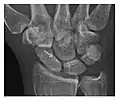

Figure 4: Dorsal triquetral fracture of the left wrist in a 30-year-old man after a trauma. (a) Anteroposterior radiograph shows a normal appearance. (b) Lateral radiograph of the same wrist demonstrates a chip fracture off the dorsal aspect of the triquetrum (arrow).[1]